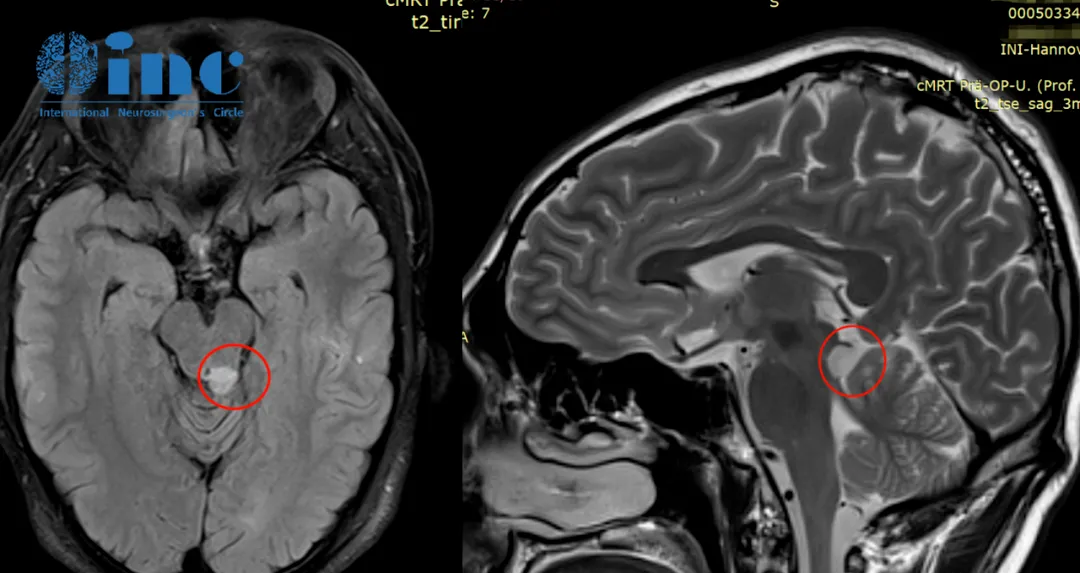

33岁的周老师,因频繁头痛头晕就医核磁共振检查结果显示中脑背侧占位,病变大小约1cm,考虑为低级别胶质瘤可能大。因为病变位于脑干,手术风险极大,术中稍有差池都可能直接造成高位瘫痪,国内就医后被建议谨慎考虑治疗方案或选择保守治疗。

赴德治疗过程:2020年成功接受手术,诊断为左侧脑干(中脑顶盖区)的低级别胶质瘤。手术过程:半坐位,经显微镜下全切肿瘤,术中全程电生理监测,手术顺利无神经缺损。术后第1天迁出ICU,回到普通病房,周先生可在普通病房自行用餐,术后第2天,周先生在医护人员的帮助下下床行走。术后第5天,周先生顺利出院。在这样的“手术禁区”,不但没有发生严重的、不可逆的神经损伤甚至可以说几乎没有什么症状,并没有在ICU多留,术后第五天竟然就能出院了,“就像做了个小手术一样”。